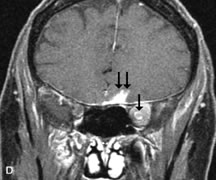

On MRI, uveal melanomas have a typical appearance that helps to differentiate them from other primary and secondary intraocular tumors as well as choroidal detachments. Pigmented melanomas are hyperintense on Tl-weighted images, hypointense on T2-weighted studies, and hyperintense on proton density–weighted examinations (Fig. 24).30,31,50,80–82 These signal characteristics have been attributed to the paramagnetic properties of melanin because of stable free radicals that shorten the T1 and T2 relaxation times. Moderate enhancement is seen on postgadolinium T2-weighted images. Gadolinium-enhanced T1-weighted images are particularly sensitive in detecting choroidal melanomas.83 MRI may be less sensitive in detecting extrascleral extension of tumor than echography performed by an experienced ultrasonographer.84

Fig. 24. A. T1- and (B) T2-weighted MR scans demonstrate a small nodular intraocular mass (arrows) that is very hyperintense on the T1-weighted scan and hypointense on the T2-weighted image. This signal intensity pattern is due to the presence of free radicals within melanin granules. C and D. Postcontrast fat-suppressed T1-weighted scans demonstrate homogeneous intense enhancement of the lesion and no evidence of seleral penetration or optic nerve invasion.